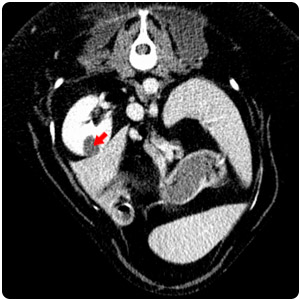

| 右腎cyst |

胸腔積液(黃)、心包囊積液(紅) |